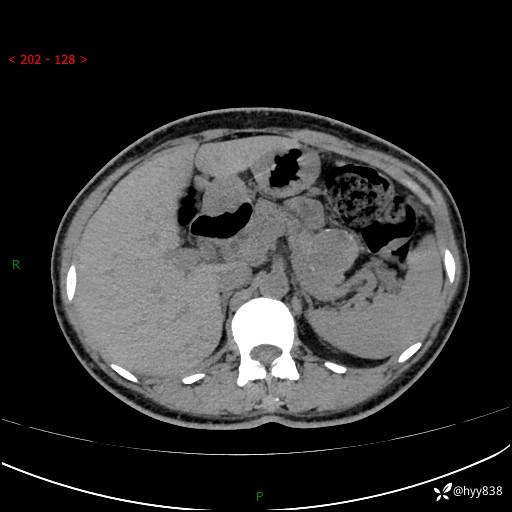

增强动脉期+静脉期

img